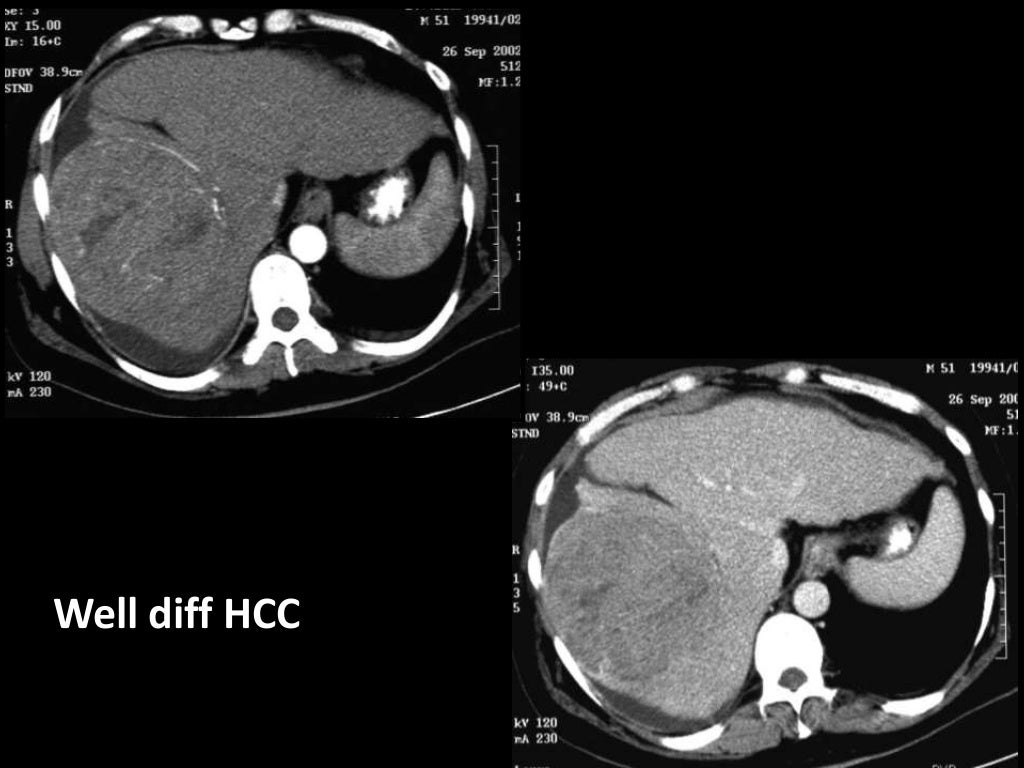

Imaging of Malignant Liver Lesions Malignant Medical Imaging Definition Imaging forms an essential part of cancer clinical protocols and is able to furnish morphological, structural, metabolic and. In contrast, tumors that stay localized and don't spread are called benign. A neoplasm is an abnormal growth of tissue that can be benign (noncancerous) or malignant (cancerous). A malignant tumor is a group of diseased cells defined by one of three. Malignant Medical Imaging Definition.

From www.slideshare.net

Imaging of Malignant Liver Lesions Malignant Medical Imaging Definition A malignant tumor is a group of diseased cells defined by one of three characteristics: Doctors use imaging tests to take pictures of the inside of your body. Benign tumors (noncancerous neoplasms) usually grow. In contrast, tumors that stay localized and don't spread are called benign. Radiologist yolanda bryce (right) and ultrasound supervisor van castor are part of a team. Malignant Medical Imaging Definition.

Imaging of Malignant Liver Lesions Malignant Medical Imaging Definition Imaging is able to spatially map key cancer features and tumor heterogeneity improving tumor diagnosis, characterization, and management. Imaging tests can be used to look for cancer, find out how far it has spread,. Uncontrolled growth, invasion and damage of healthy cells, or metastasizing (spreading) to. Doctors use imaging tests to help find and diagnose. Imaging forms an essential part. Malignant Medical Imaging Definition.